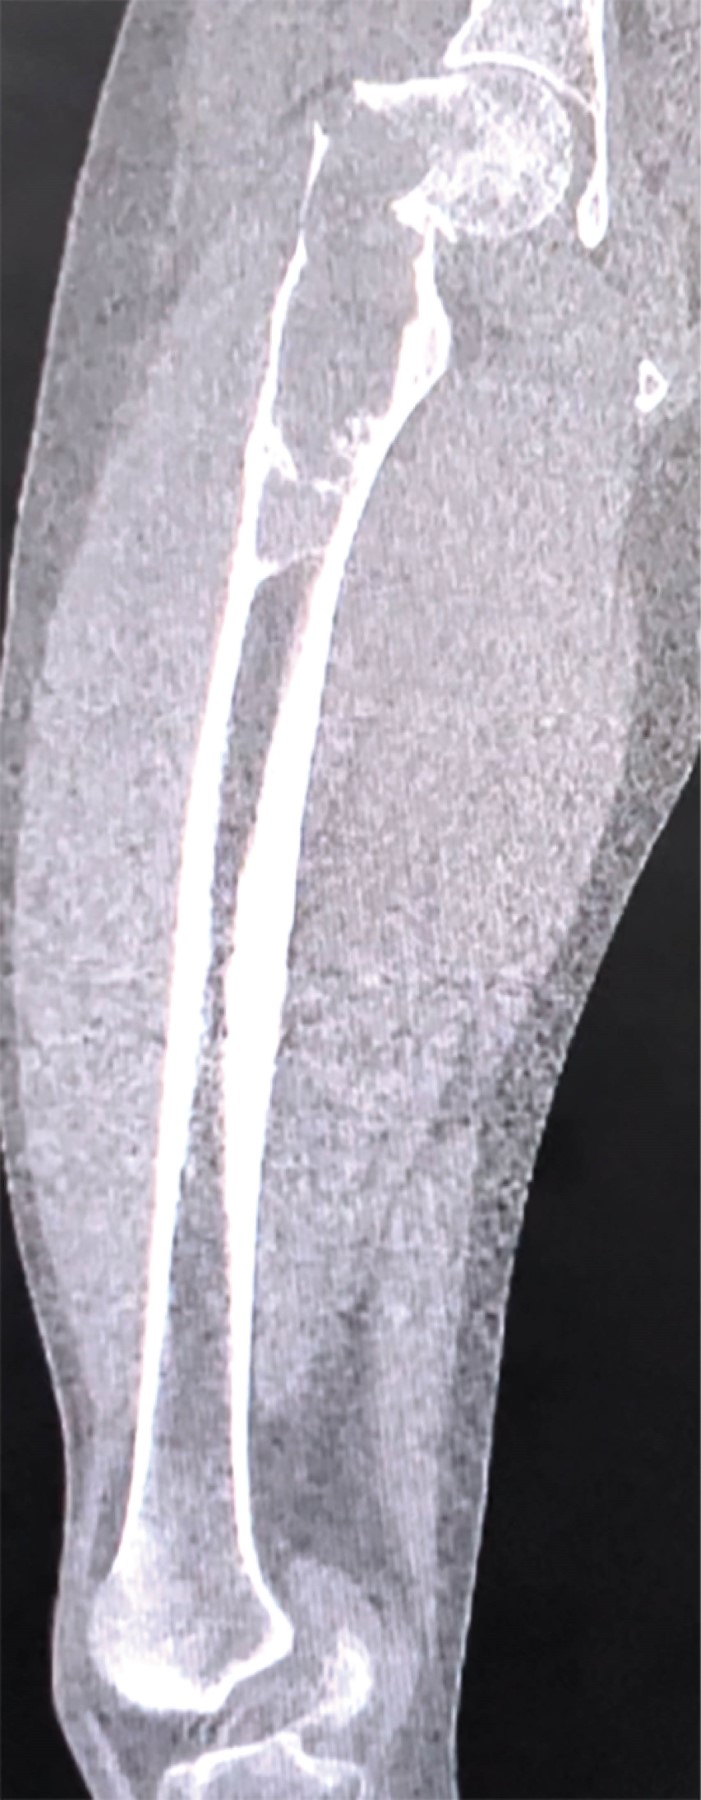

Se realizaron radiografías de pelvis y de fémur, que revelaron una fractura basicervical de fémur derecho Garden II Pauwells III AO 31B2.3r, con un patrón lítico de destrucción geográfica y un margen esclerótico bien delimitado que se extendía hacia el fémur distal aproximadamente 14 cm, sin evidencia de reacción endóstica o perióstica (Figura 1). Estas imágenes eran compatibles con una lesión de lento crecimiento, que necesitaba confirmación mediante histopatología, ya que, como se mencionó previamente, a pesar de que el paciente cuenta con antecedente de DF, existen otras entidades, algunas de comportamiento biológico maligno, de las cuales debe hacerse diagnóstico diferencial. Como estudio complementario, se realizó una tomografía simple de fémur derecho, ya que nos permite delimitar perfectamente los bordes de la tumoración para la planeación quirúrgica, así como precisar el patrón de destrucción lítico y el adelgazamiento del hueso cortical (Figura 2). Los parámetros del metabolismo óseo se encontraban dentro de valores normales.

Figura 2